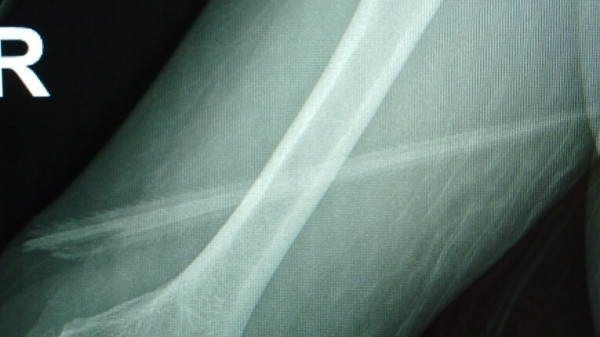

На рентгеновских снимках было видно, что шип пронзил руку женщины, как кинжал: вошел чуть выше правого локтя и вышел почти из-под мышки, едва не задев артерию. "Оглядываясь назад, я чувствую себя так, будто выиграла в лотерею", - призналась женщина.